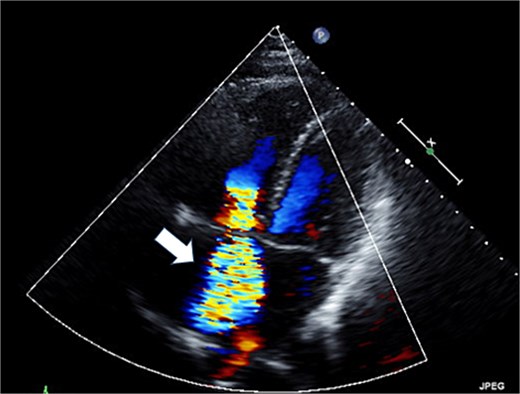

The patient was a 50-year-old female with pulmonary (PV) and tricuspid valve (TV) regurgitation. At 8 years old, she received RVOT reconstruction due to PV stenosis. When she was 44 years old, transthoracic echocardiography revealed PV regurgitation and PVR (INSPIRIS 19 mm; Edwards Lifesciences Corporation, Irvine, CA, USA) and tricuspid annuloplasty (Physio annuloplasty ring 28 mm; Edwards Lifesciences, Irvine, CA, USA) was performed. After 3 years of this operation, she gradually became complained of palpitation and syncope. Transthoracic echocardiography revealed severe tricuspid regurgitation due to leaflet tethering and moderate pulmonary regurgitation caused by dysfunction of one of the tissue valve leaflets (Figs 1 and 2). Cardiac magnetic resonance imaging showed right ventricular enlargement (right ventricular end-diastolic volume index; 97.5 ml/m2). Finally, we decided to perform a redo PV and TV replacement.

Preoperative transthoracic echocardiography: moderate pulmonary regurgitation. The regurgitant jet is indicated by the white arrow.